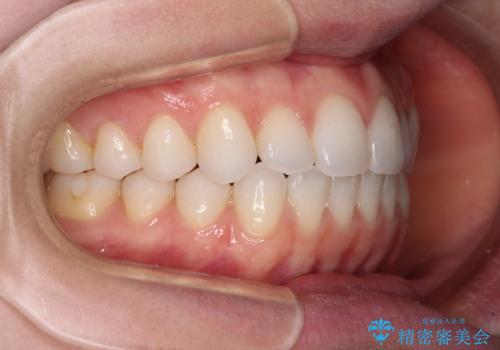

上下前歯が接触しない オープンバイトをインビザラインで改善

- 前歯の上下スペースによる食べにくさを気にして来院された患者様です。

インビザラインにより上下の前歯の隙間を閉じていくこととしました。

上下の奥歯を圧下させるようにすることで、前歯を接触させるように計画しました。

上下の隙間に舌が入り込むことがオープンバイトの原因であったため、舌の筋肉のトレーニングも並行して行い、後戻りの抑制を図りました。